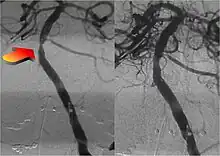

Parallel to the development of catheters, in the radiology and neuroradiology units, image technology dramatically improved: Charles Mistretta in 1979 invented digital subtraction angiography (DSA), the technique currently in use. It consists of performing skull radiography under basic conditions which are then "subtracted" to the image after contrast media injection, to provide an image where only brain vessels are displayed, with great improvement in the diagnostic potential.

Endovascular repair of cerebral aneurysm